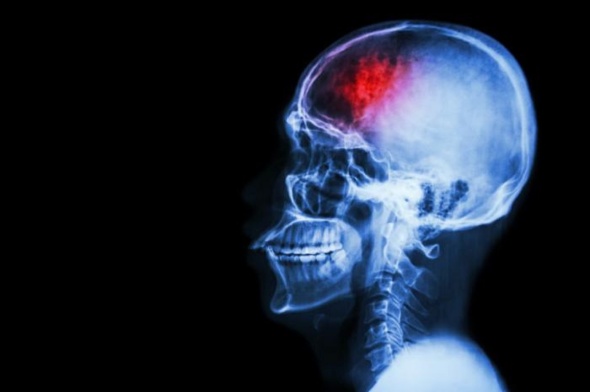

Stroke-like brain damage is reduced in mice injected with omega-3s

A stroke can happen at any age, and as with anything that involves the brain, a few seconds can be life altering. Usually the rule is time lost is brain lost, but there might be some good news regarding that, researchers found that omega-3 fatty acids reduced brain damage in a neonatal mouse model of stroke.